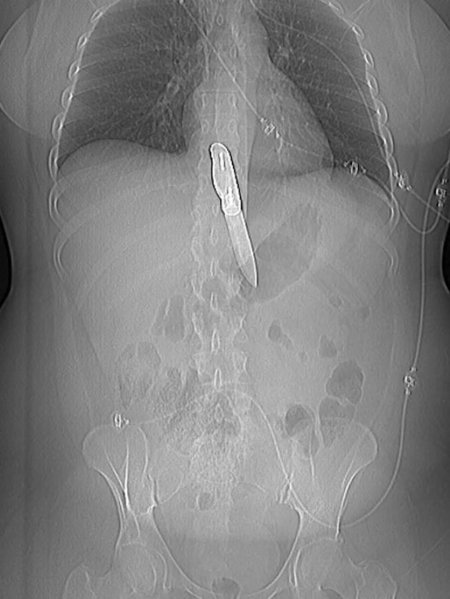

Рентгеновский эффект создает фантастические композиции в этих фотографиях девушки, чье тело становится прозрачным, демонстрируя скелет и внутренние органы. Она позирует в разных позах, ее силуэт светится загадочным свечением. Каждый кадр передает атмосферу научной фантастики и медицинского искусства. Ее кожа кажется полупрозрачной, позволяя увидеть кости и мышцы. Фотографии рассказывают о хрупкости человеческого тела и его внутренней красоте. Девушка то стоит в задумчивости, то делает грациозное движение. Эти иллюстрации вдохновляют на размышления о человеческой анатомии и уязвимости. Каждая картинка - это момент прозрения, когда внешнее уступает место внутреннему. Девушка воплощает образ современной Медузы, сочетающей красоту и загадочность.

Сквозь материю: тайны анатомии